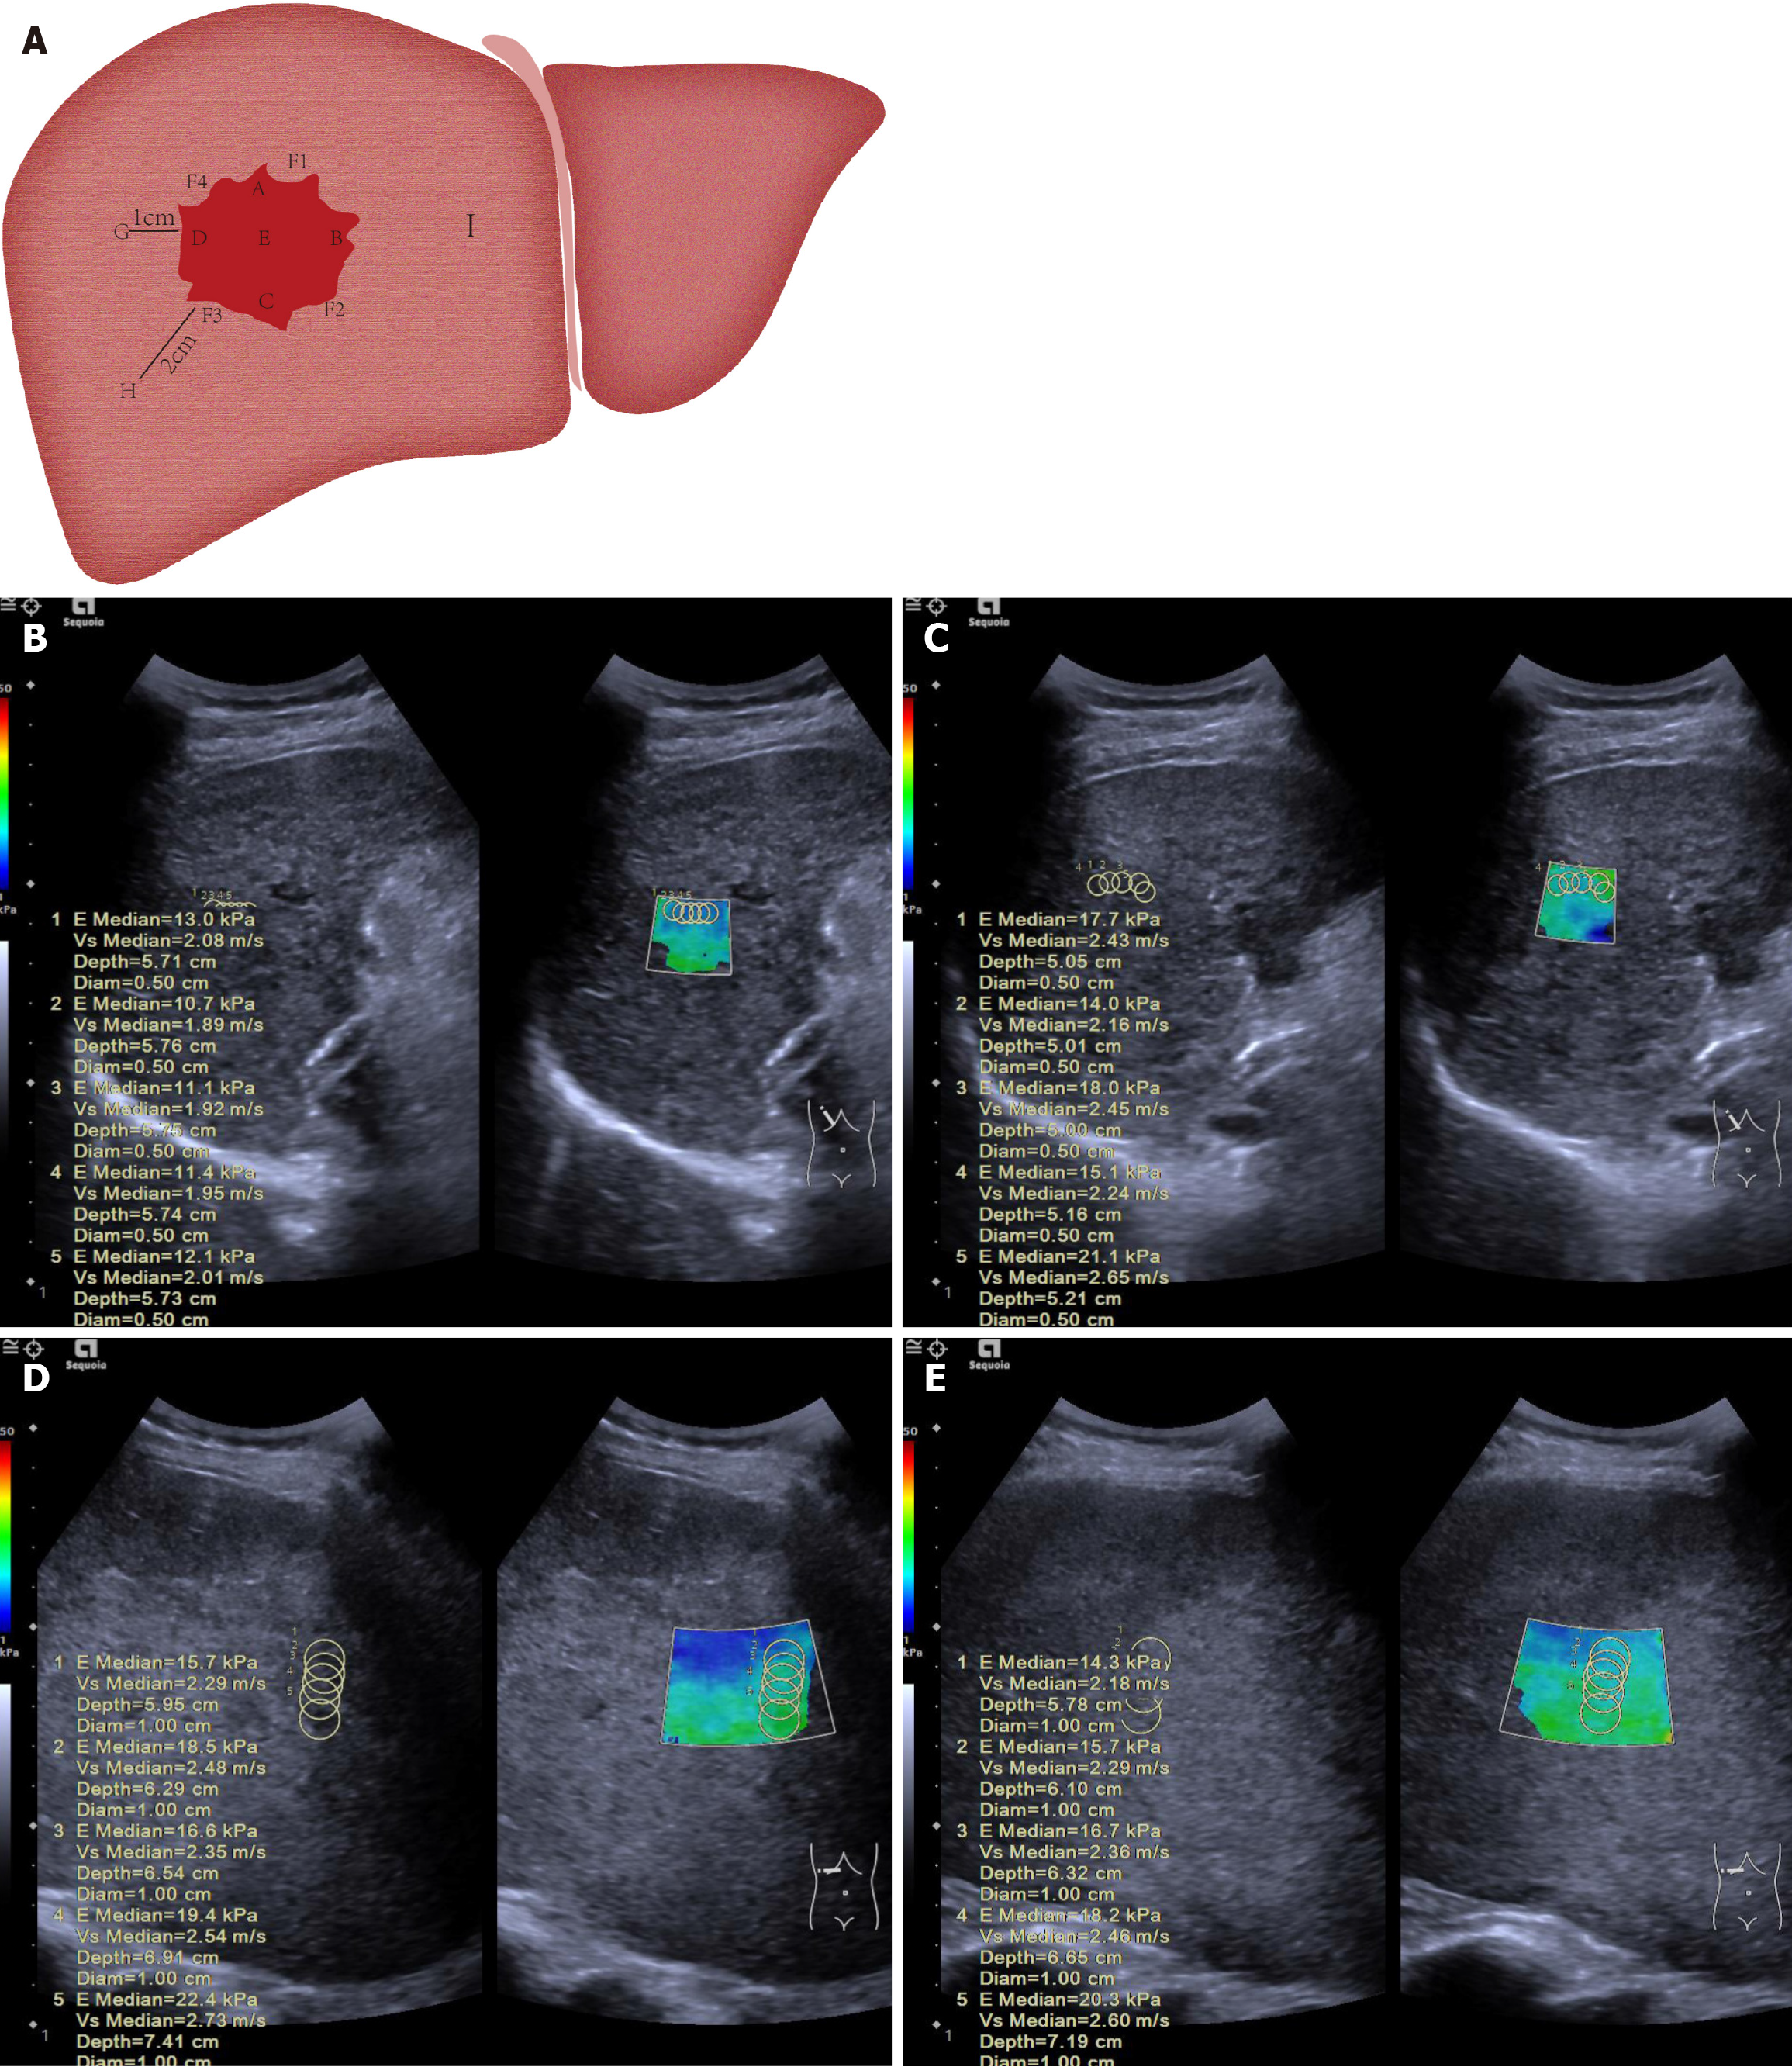

Figure 2 Diagram illustrating measurement of liver tumor and surrounding tissue stiffness.

A: The 12-point clock-face method was used to define points within and around the tumor: A (superior, 12 o’clock, closest to transducer), B (left lateral, 3 o’clock), C (inferior, 6 o’clock, furthest from transducer), D (right lateral, 9 o’clock), and E (central). Peritumoral tissue (normal liver adjacent to the tumor capsule) was sampled at F1 (2 o’clock), F2 (5 o’clock), F3 (8 o’clock), and F4 (11 o’clock). Normal liver was sampled at G (1 cm), H (2 cm), and I (> 2 cm) from the tumor margin; B: A 52-year-old male patient had a pre-treatment mean stiffness of 11.7 kPa in the anterior part of the tumor; C: After treatment, the mean stiffness increased to 17.1 kPa, with stiffness also rising at other measurement points, indicating ΔT > 0. This patient had no tumor progression at 26 weeks, confirming treatment effectiveness; D: A 48-year-old male patient had a pre-treatment mean stiffness of 18.5 kPa in the anterior part of the tumor; E: After treatment, the stiffness dropped to 17.0 kPa, with similar decreases observed at other points, indicating ΔT < 0. This patient showed tumor progression at 12 weeks.